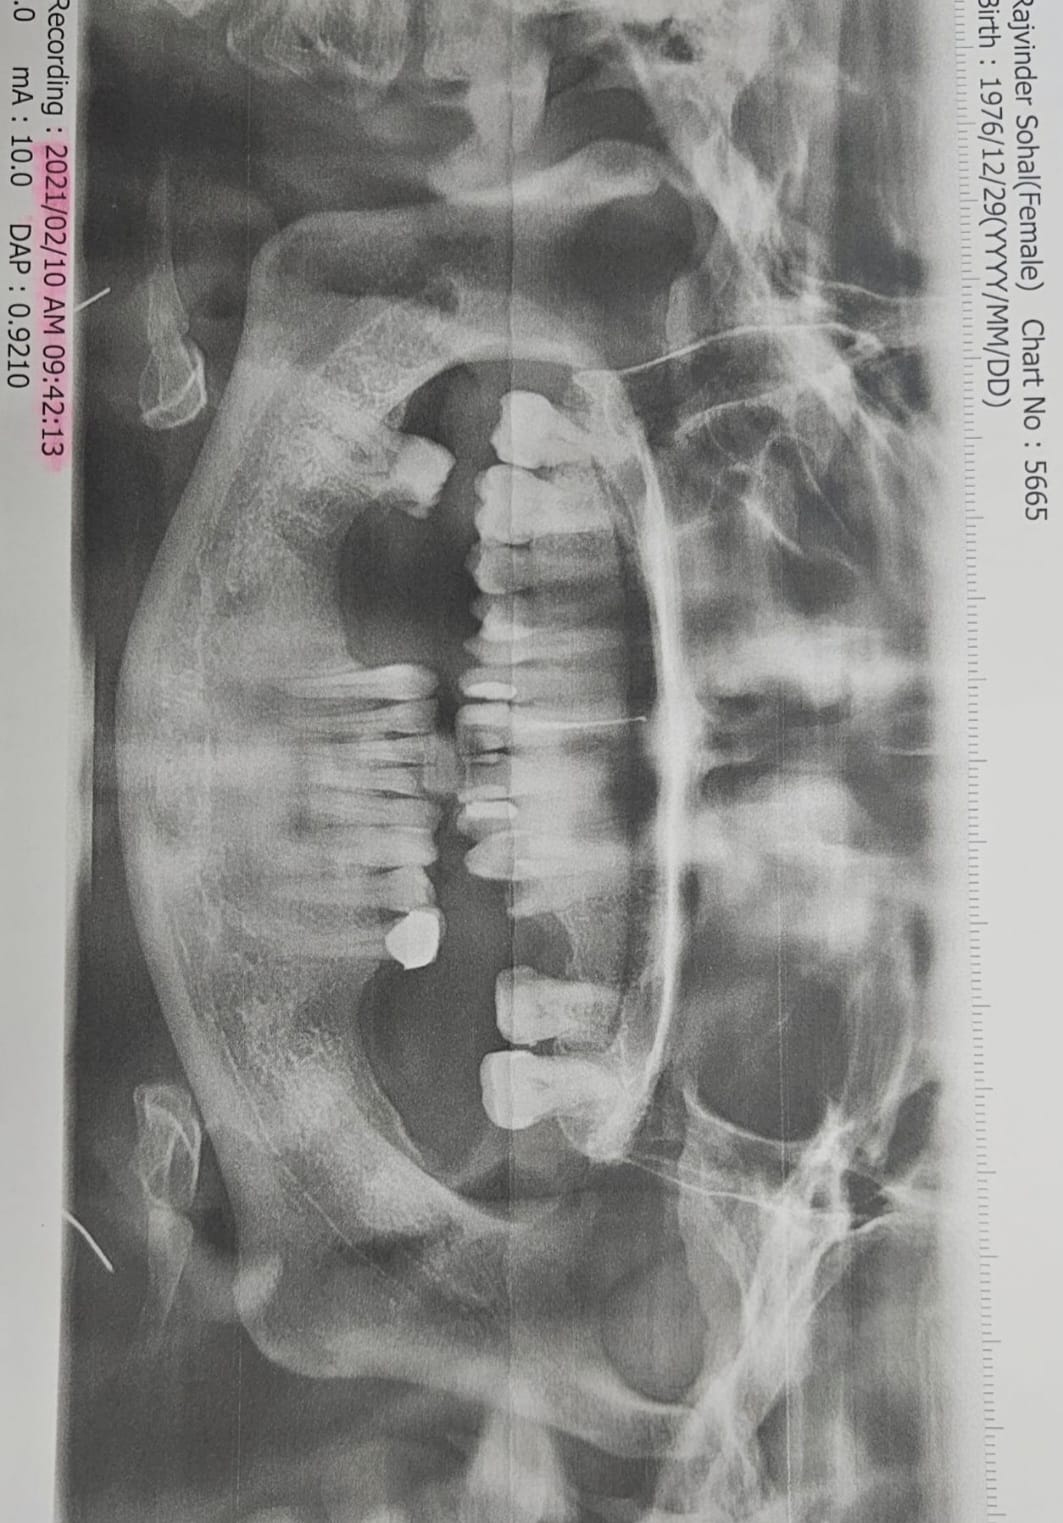

Full Mouth Implant Case